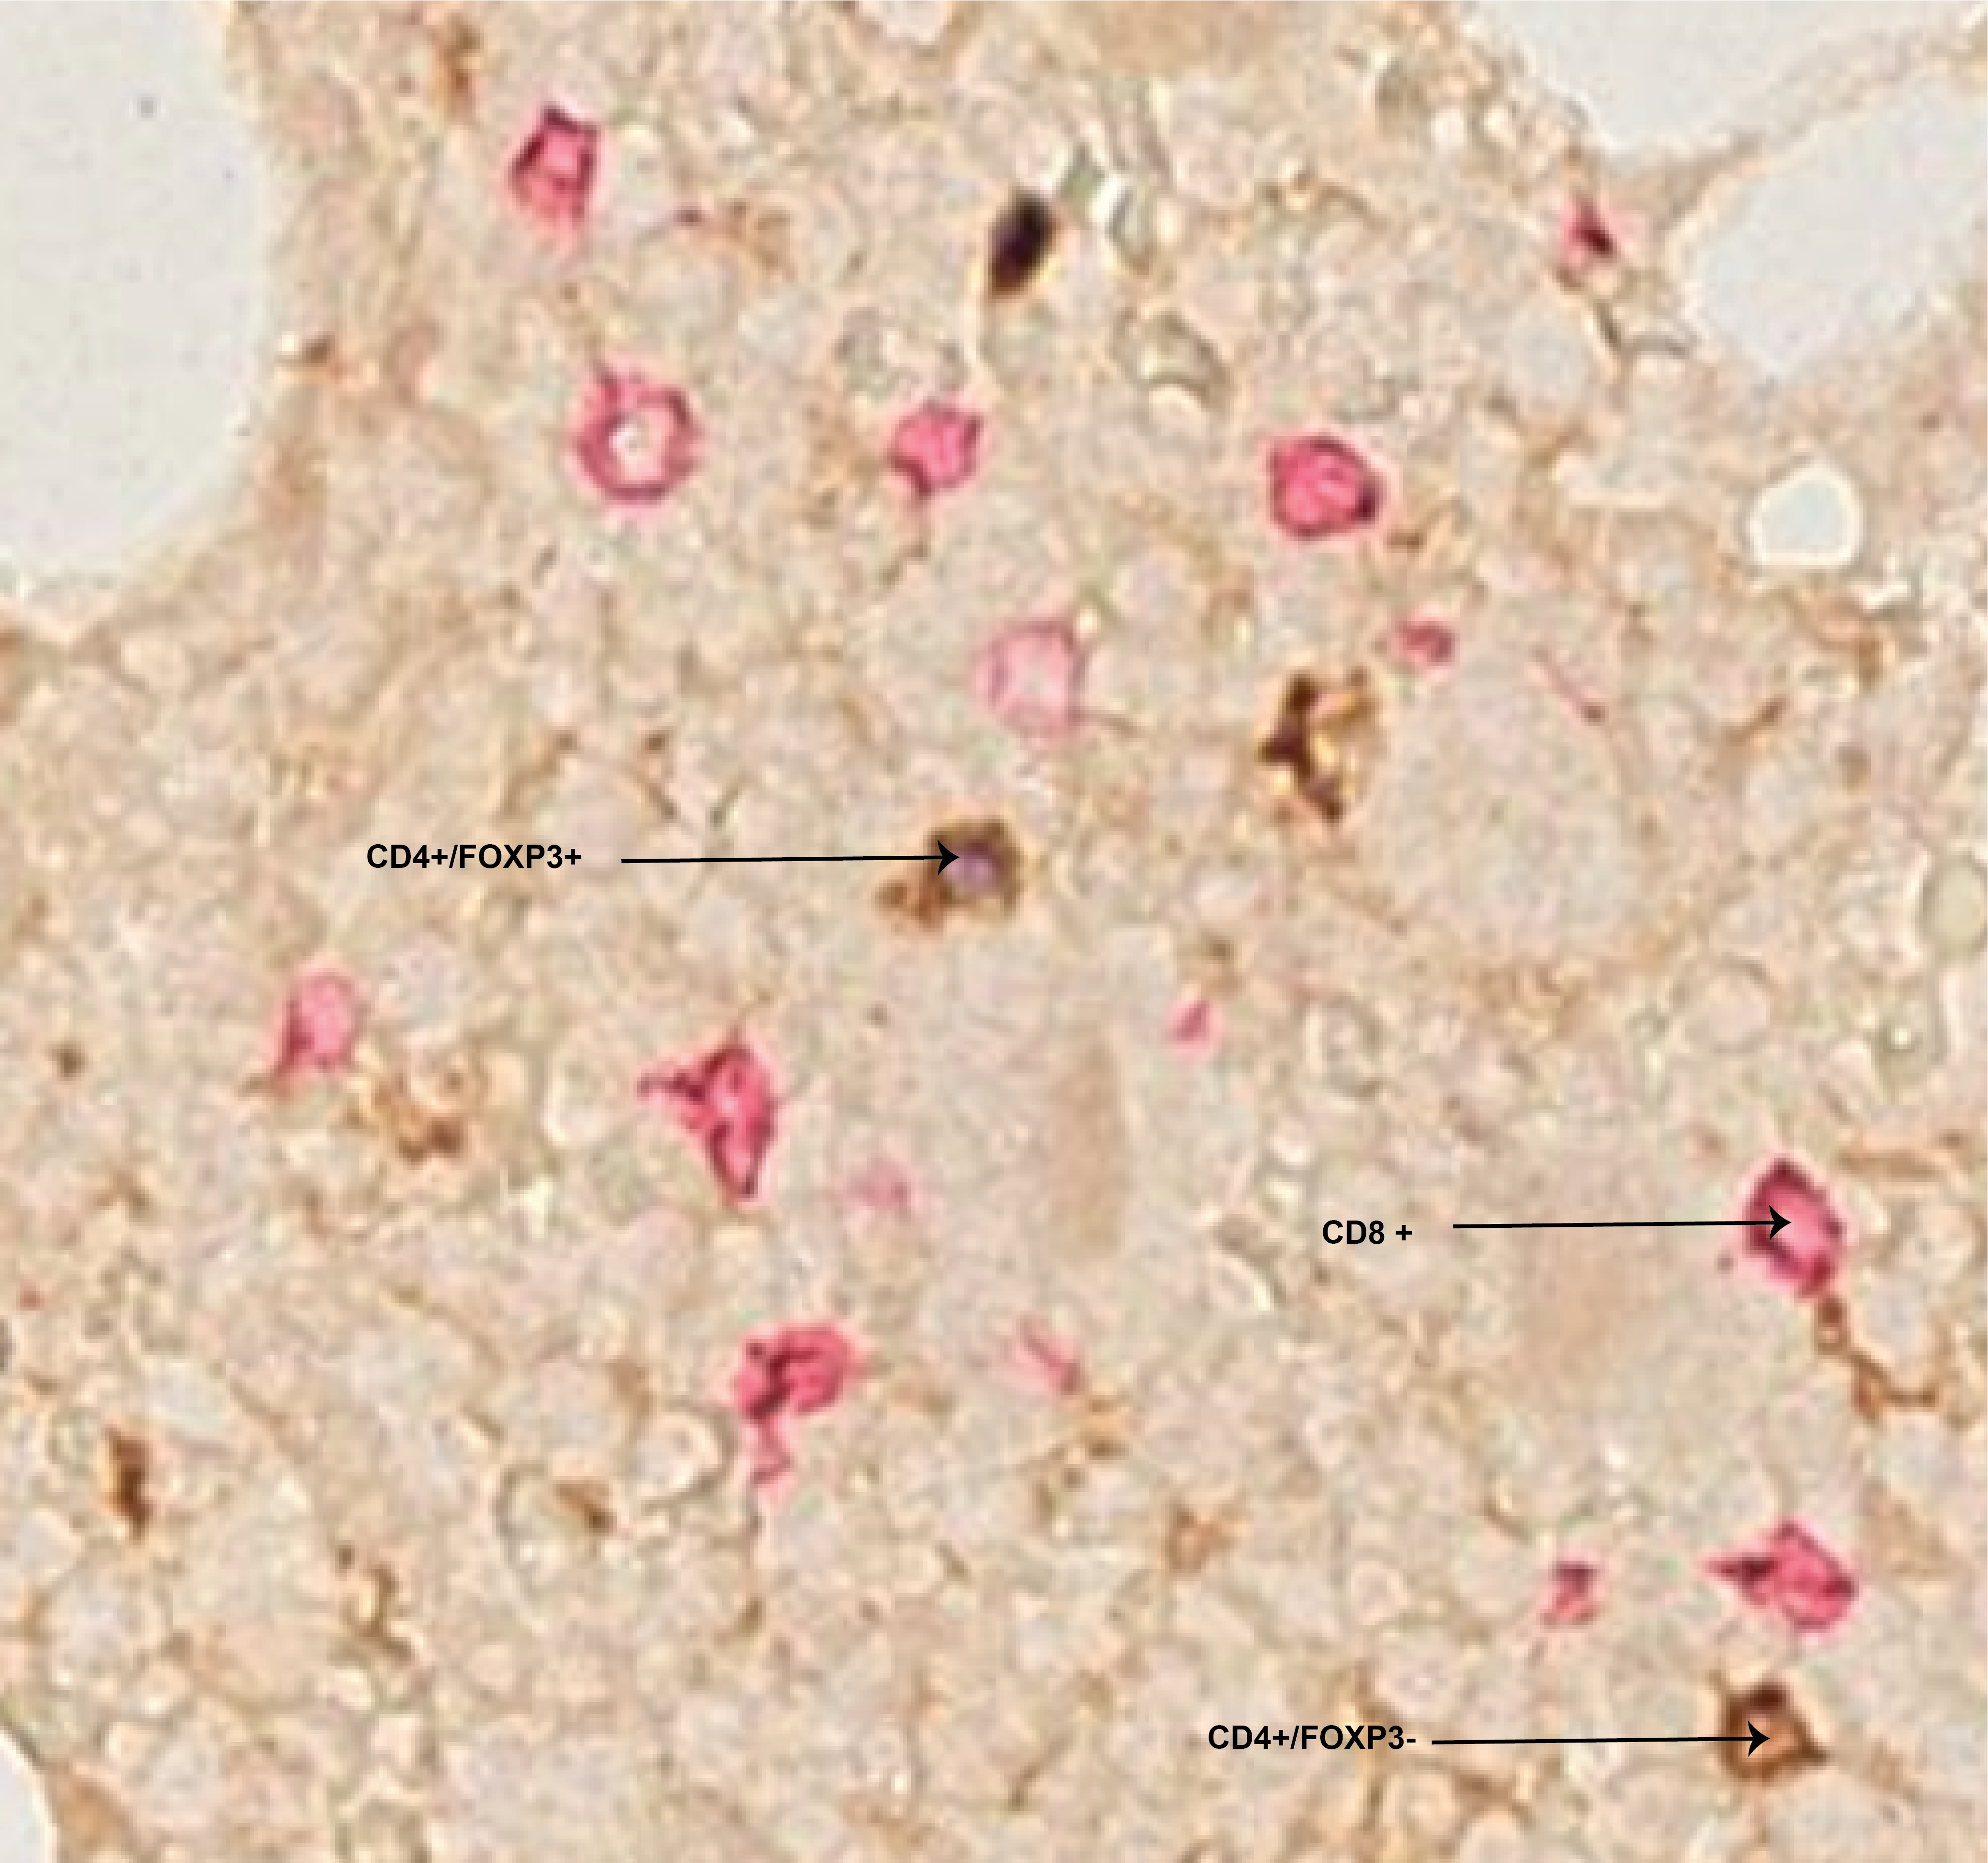

In digital pathology, cell detection and classification are the first step to assessing tumour load, surrounding micro-environment and immune phenotypes [1]. Multiplex immunohistochemistry (mIHC) is a staining method that allows simultaneous examination of multiple cell markers in a single image, where each cell is represented by a unique color or color combinations (Fig. 1). Intrinsically, some cell types are fewer compared to others. For example, in bone marrow trephine samples, the number of CD4+/FOXP3- effector and CD4+/FOXP3+ regulatory T cells is lower than that of CD8+ T cells ( Fig. 1). This imbalance causes instability and bias on the performance of discriminative models.

Our dataset contains newly diagnosed myeloma bone marrow mIHC whole slide images. It contains CD8+, CD4+/FOXP3- and CD4+/FOXP3+ cell types (Fig. 2a). To train and evaluate the proposed method, a total of 8014 cells were annotated in different regions of the whole slide images by experts by putting a dot at the center of a cell (Fig. 2b). Table 1 shows training, validation, and testing split.